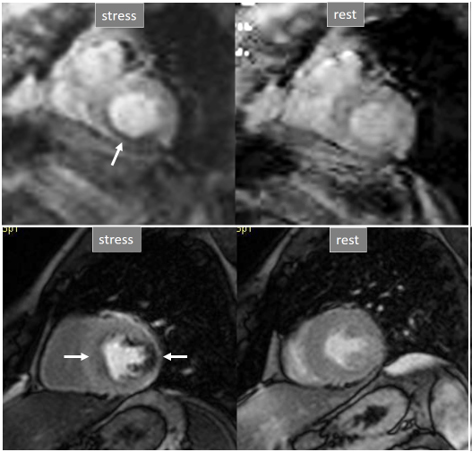

Perfusion defects in different territories can be detected in case of multivessel disease (Fig. 7) and, in patients with severe 3-vessel CAD, the perfusion study may show a global, intense, persistent defect which is readily recognizable (Fig. 8).

Fig. 8.Three-vessel perfusion defect. Stress and rest studies in a patient with severe left main and 3-vessel CAD (arrows, on the right panels) showing an inducible perfusion defect in most, if not all, of the myocardial segments during vasodilatory stress.